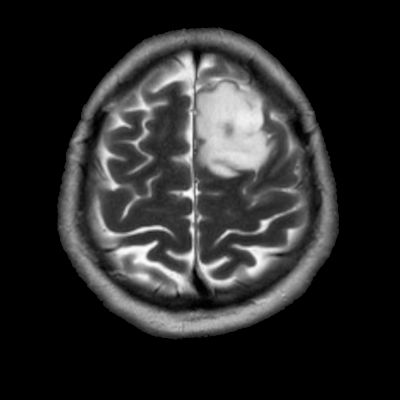

- Sol frontal kortikal-subkortikal yerleşimli aksiyel T2A görüntüde hiperintens sinyal özelliği gösteren (oklar) ve FLAIR görüntüde sinyali ağırlıklı olarak baskılanan (oklar) kitlesel lezyon izleniyor. Lezyon T1A görüntüde hipointens olup post-kontrast T1A görüntüde bu düzeyde patolojik kontrastlanma izlenmiyor (oklar).

- FLAIR’de T2’ye benzer şekilde hiperintens görünür. Ancak T2–FLAIR mismatch bulgusu, bu tümör tipi için oldukça karakteristiktir.

- T2–FLAIR mismatch bulgusu, T2AG’de homojen hiperintensite ile FLAIR görüntüde santral sinyal baskılanmasının ve çevrede hiperintens halka görünümünün bulunduğu bir fenomendir. Bu bulgu, özellikle IDH-mutant, 1p/19q kodelesyonu olmayan astrositomları tanımlamada oldukça özgül bir biomarker olarak literatürde vurgulanmıştır. Ayırıcı tanıda akla gelmesi gereken oligodendrogliomlarda T2/FLAIR mismatch bulgusu genellikle görülmez.

- Olgumuzda T2-FLAIR mismatch bulgusu mevcut olup, opere edilmiş ve tanısı histopatolojik olarak konulmuştur.